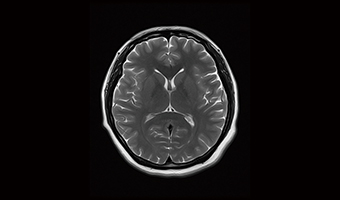

Application Images

Full Size